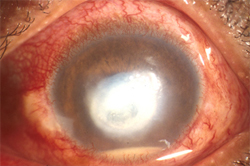

The cornea is the clear window in front of the eye. If it is not clear the patient can’t see. This patient has a corneal ulcer that requires urgent treatment.